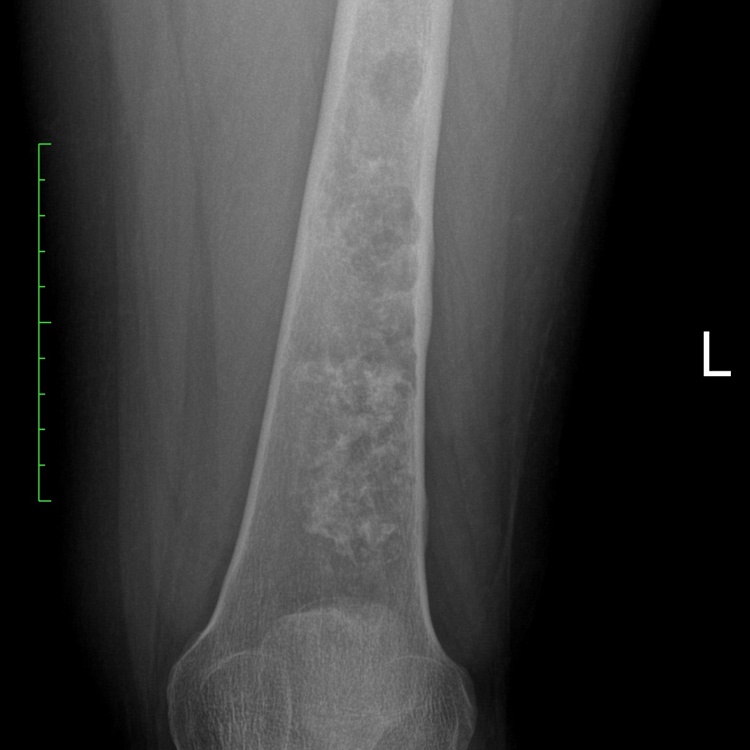

7A) Chondrosarcoma Case 1 Plain AP X Ray Of The Left Femur JW2

Conventional Chondrosarcoma is a bone sarcoma (primary bone cancer) that is made up of cartilage tissue. Conventional means it is the most common type of a chondrosarcoma as there are multiple different types. Cartilage is a type of tissue that lines your joints and allows movement between bones and joints. This type of tumor occurs primarily in the femur, humerus, scapula and pelvis. A chondrosarcoma grows and destroys the bone, adjacent joints and surrounding muscle tissues. Since it is cancerous it can spread to other areas in the body. Conventional chondrosarcoma is classified according to their grade: Low grade, Intermediate grade, High grade. Low grade is slow growing and rarely if ever spread to other body parts. High grade grow rapidly and spread 30-50% of the time.

• • The work-up is often consist of a physical examination, X-rays, CT scans, MRI, and sometimes bone scans are required. CT scans can be used to check for subtle mineralization that may help with the diagnosis

Radiographic imaging is used to help form a diagnosis. These include X-Ray, MRI, CT and Bone Scans